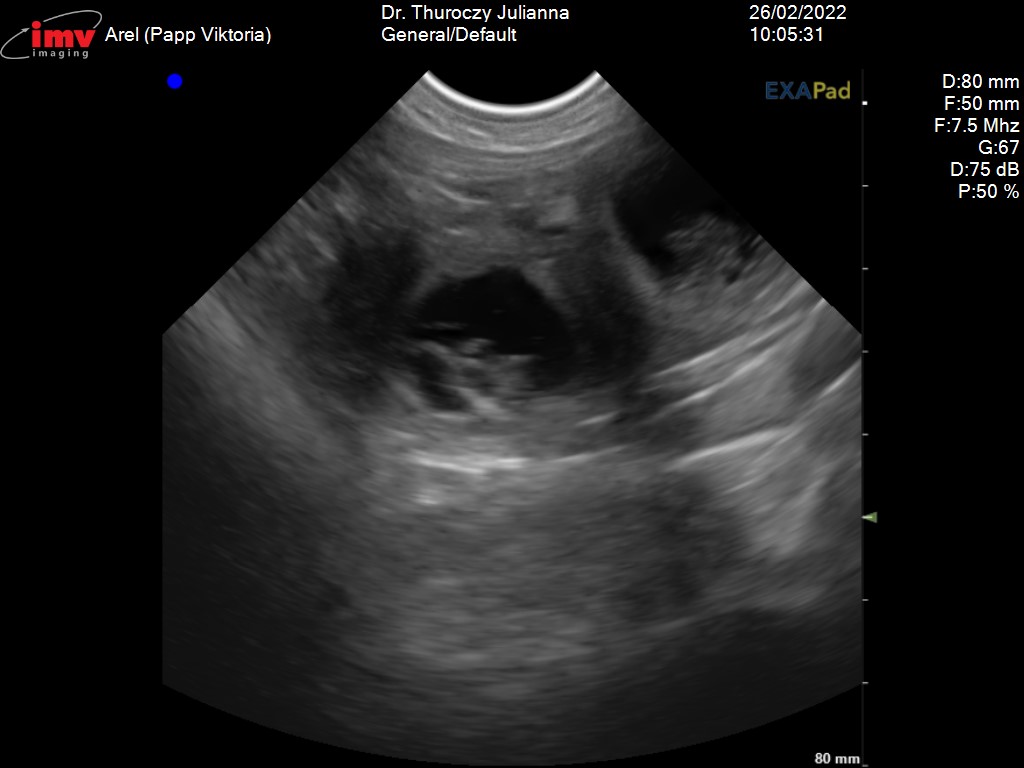

Az élet egyik nap elvesz a másik nap ad. A szombati ultrahang megerősítette hogy Arel és Beso pároztatása sikeres volt. Arel vemhes. Köszönjük Joanna a bizalmat. Gratulálunk Besónak, ügyes volt.

Kiskutyák születése várható